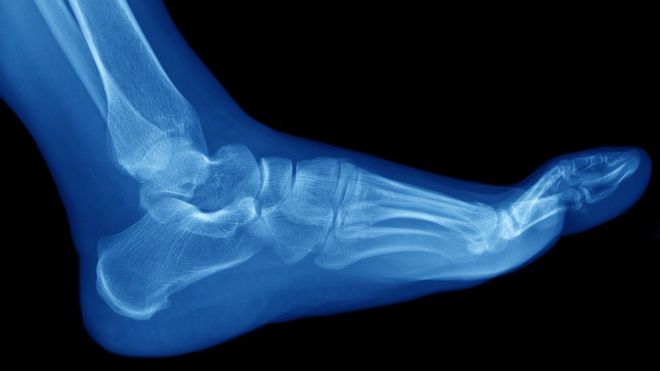

Las fracturas por estrés suelen ocurrir en los huesos de la parte inferior de la pierna y el pie

Las fracturas por estrés suelen ocurrir en los huesos de la parte inferior de la pierna.

Este tipo de roturas están normalmente asociadas al deporte y suelen ocurrir en los huesos de la parte inferior de la pierna y el pie, como la tibia y el peroné, los metatarsos, el talón y el tobillo.